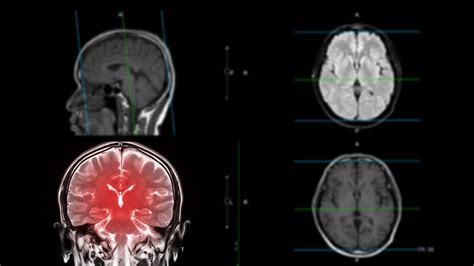

Medical brain scan representation

CTE is a progressive brain condition thought to be caused by repeated hits to the head and repeated episodes of concussion. Unlike a standard concussion, which is an acute injury, CTE involves the progressive accumulation of a protein called tau within the brain, which leads to the death of brain cells over time. Because the definitive diagnosis of CTE can only be performed post-mortem, clinicians are currently focused on identifying symptoms early and providing supportive care. The lack of a definitive diagnostic tool for living patients remains a primary hurdle in establishing a standardized CTE disease treatment protocol.